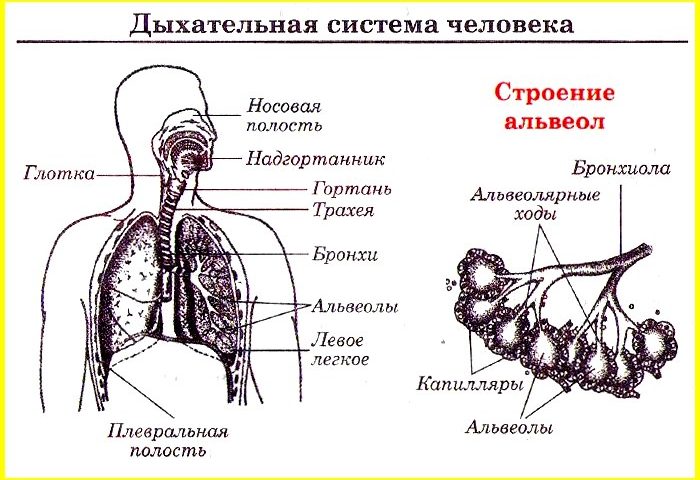

Схема дыхательной системы человека: а — общий план строения; б — строение альвеол; 1 — носовая полость; 2 — надгортанник; 3 — глотка; 4 — гортань; 5 — трахея; б — …

Дыхательные пути представляют собой систему трубок, просвет которых формируется благодаря наличию в них костей и хрящей . Внутренняя поверхность дыхательных путей …

Дыхательнаясистемачеловекасостоитизтканейиорганов,обеспечивающихлегочную вентиляциюилегочноедыхание .К воздухоносным путям относятся: нос, полость носа, носоглотка, …

Дыхательная система (дыхательный аппарат), systema resperatorium, состоит из дыхательных путей и парных дыхательных органов - легких . Дыхательные пути …